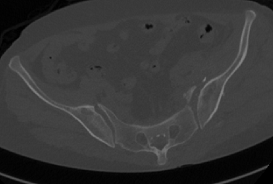

术前CT和术后CT比较

近日,市四医院骨一科收治了一位特殊患者,该患者因车祸伤致骨盆多处骨折,经CT检查后,发现该患者骨盆有大大小小的骨折达8-10处,左侧骶髂关节明显脱位,双侧耻骨骨折。

整个手术1小时内完成,通过术后CT影像证实3D打印导航模板引导骶髂螺钉置入安全、准确、创伤较小,手术时间短,患者也很快得到了较好的恢复。